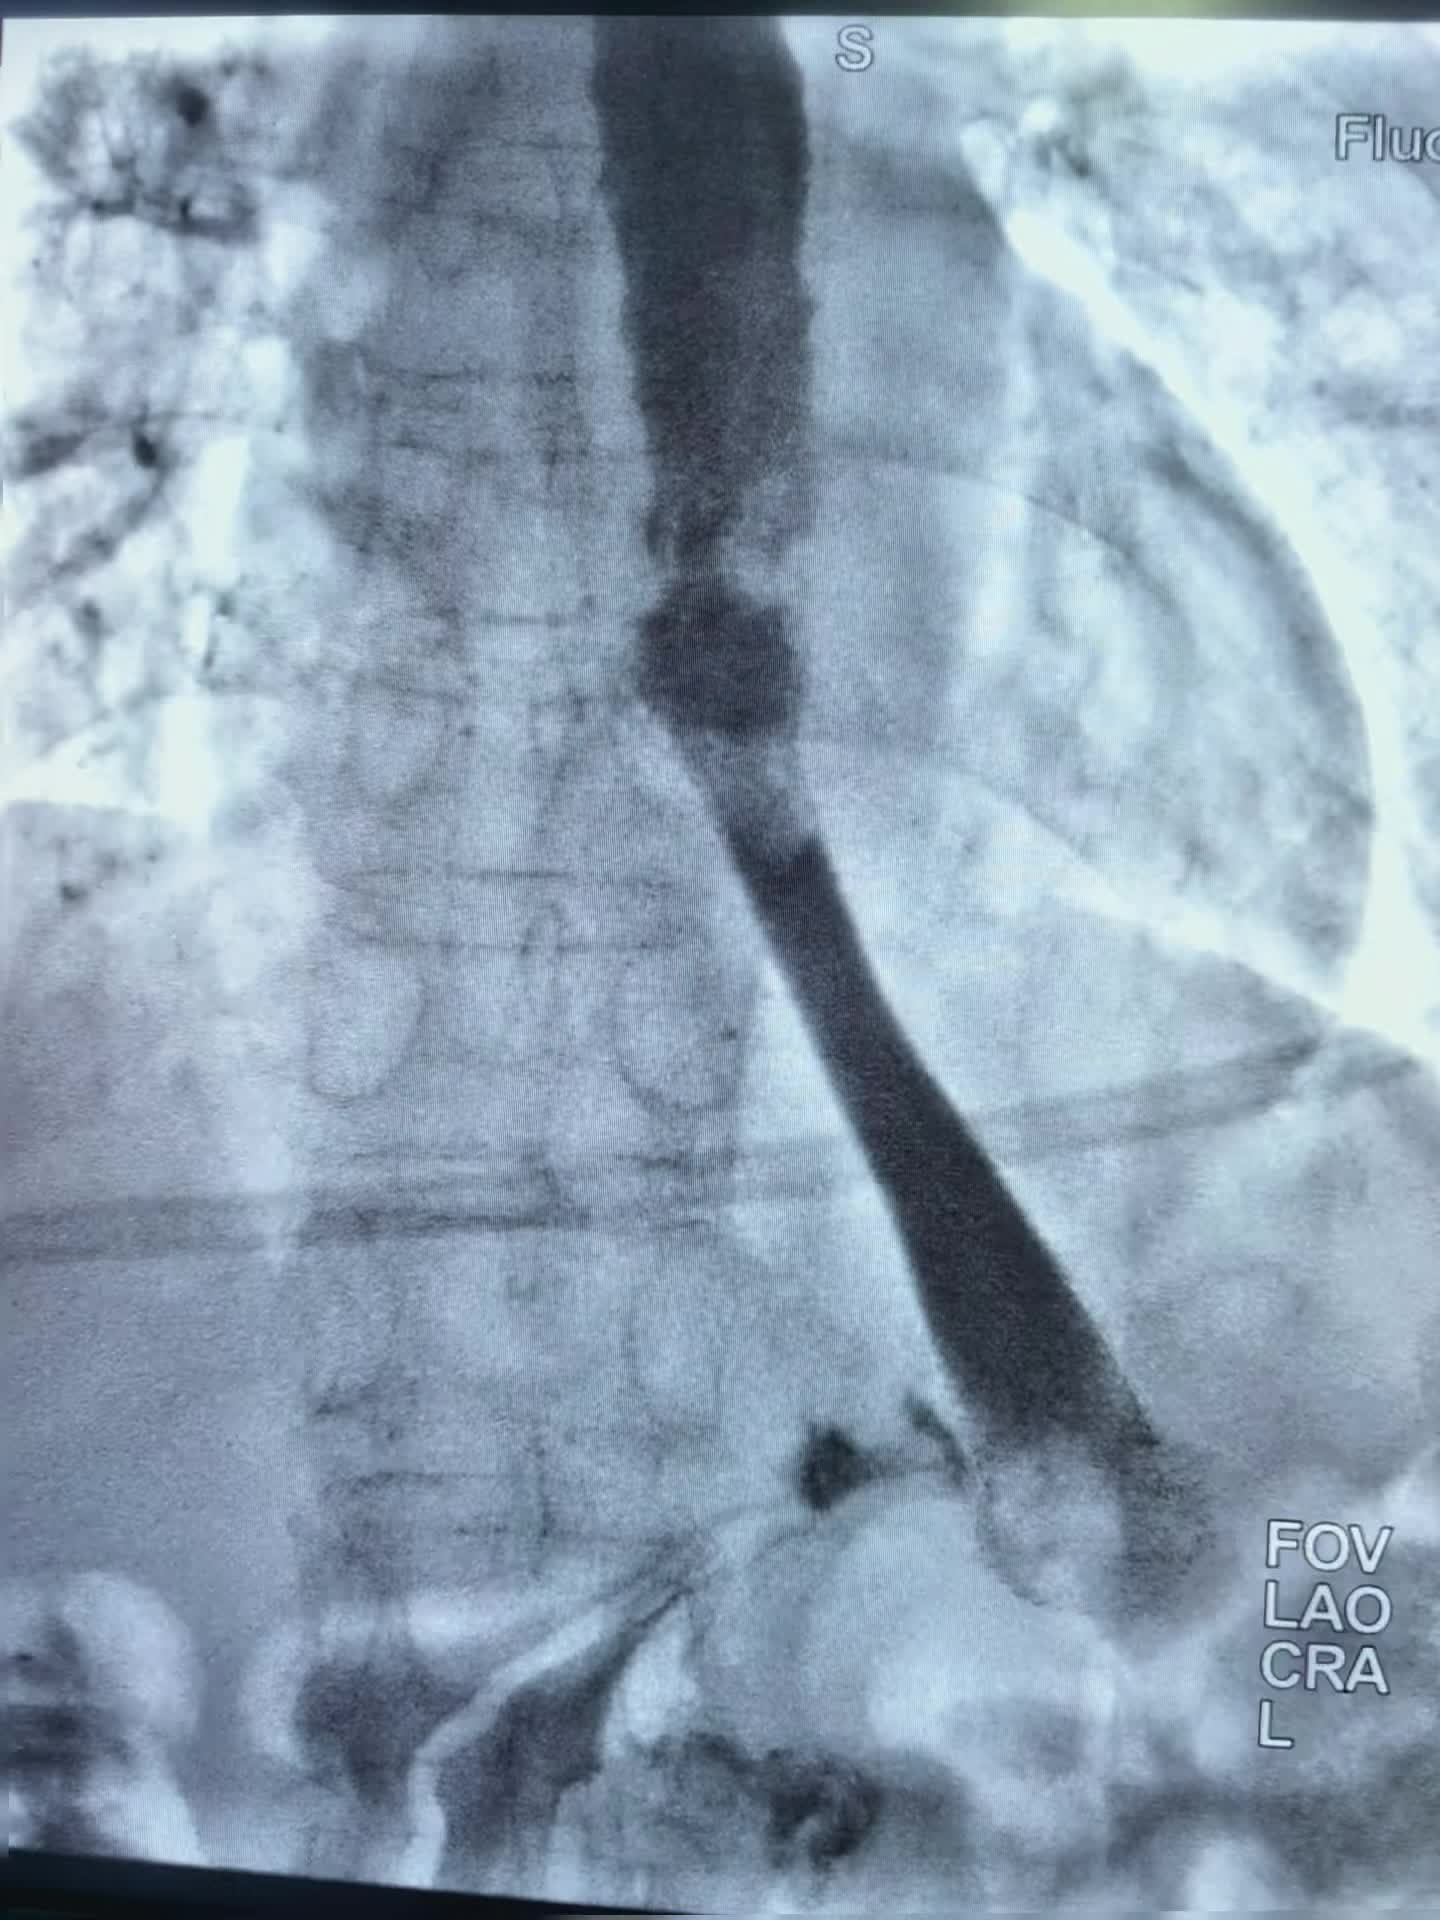

上午第一台78岁老年男性贲门癌患者,突发食管梗阻不能进食水,行球囊扩张,食管支架置入术,术即可恢复饮食。 第二台:食管癌术后3年再次进食哽咽,食管吻合口狭窄伴肠管膈肌处狭窄。单纯行球囊扩张术,术后即可恢复正常饮食。